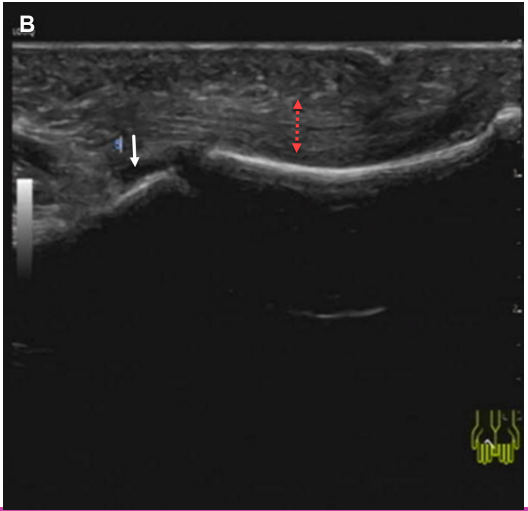

A 48-year-old woman presented with a 6-month history of progressive bilateral hand swelling, stiffness, and impaired finger extension. Physical examination revealed indurated edema and flexion contractures (Figure 1, the bottom image shows a normal palm for comparison). Laboratory tests showed peripheral eosinophilia (3.59 × 109/L), elevated ESR (85 mm/h), hypergammaglobulinemia, and positive anti-SSA antibodies. Musculoskeletal ultrasound demonstrated marked fascial thickening (5.2 mm) and mild joint effusion (Figure 2, arrows).